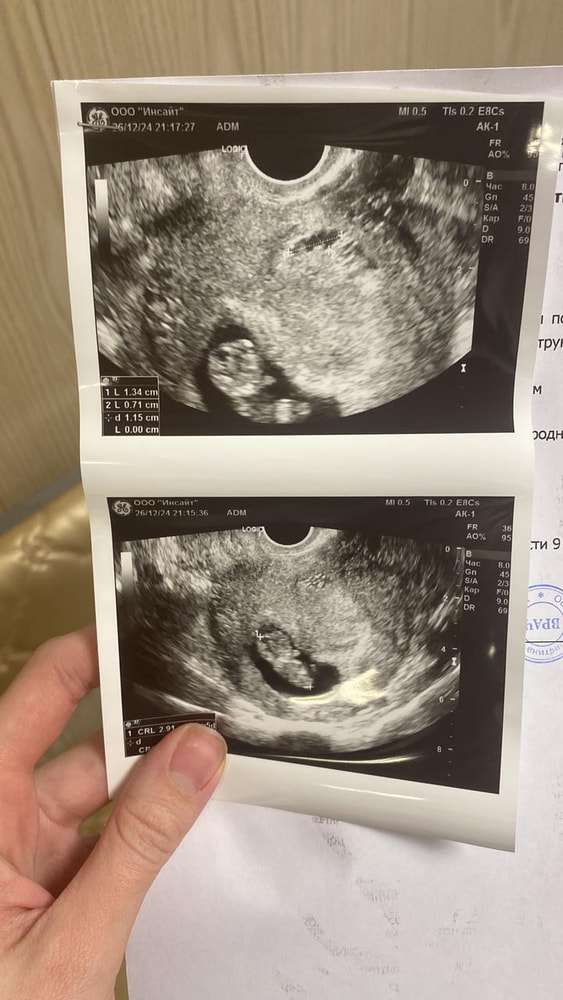

Потом одно узи, только плодное яйцо и мешочек, затем второе, и вот привет малыш🩵

Ну как обычно дальше врачи, куча анализов и ждать первый скрининг. Токсикоза не было, как такового кстати. Но не тут то было, ну не может быть все хорошо😩 Обычный день, у старшего елка в саду, сходила, пришла на работу, отработала одну клиентку, пошла в туалет и сюрприз 🤦🏻♀️ Закровило, в срочном порядке договариваюсь об узи, еду с клиенткой🙏🏻 Большое ей спасибо за это❤️

Вся тряслась, сразу плохие мысли о замершей, был же опыт такой с первой самой

И вот она красотка ГЕМАТОМА🤦🏻♀️ Все обошлось, не было госпитализации, помазало два дня и перестало.